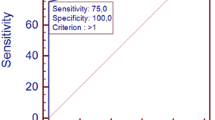

Results are summarized in Figs. 4 and 5. For the 11 patients evaluated by both techniques, MRI and MDCT studies gave similar results for the extent of late enhancement (8.8±2 and 9±2 segments, respectively, p<0.05). There was also a good correlation between the two methods in the number of segments involved (Spearman, y=(1.17)×−1.17, r=0.9167, p=0.0004). A focal distribution of late enhancement was found in six patients with both MRI and MDCT. Segment-by-segment comparison showed a high level of correlation (y=(0.93)×+0.12, r=0.90, p<0.0001). However, there were some differences between both methods in localization of detected enhancement: CT showed more enhancement in apical segments and the anterior wall while MR showed slightly more involved segments in the inferior and lateral wall.